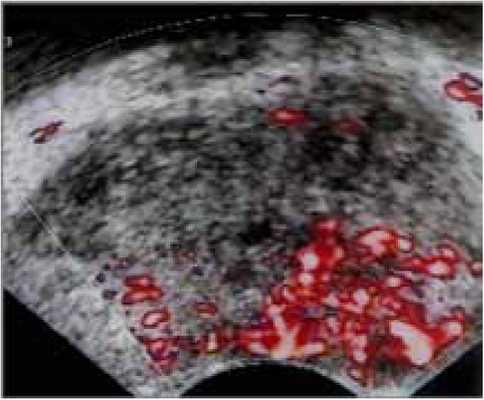

Однако, новые УЗ-технологии опровергают это мнение. Выполнение УЗИ также дает информацию о центральной, периферической части железы и о капсуле. УЗИ с допплеровским картированием, особенно при использовании эхоконтрастных средств, позволяет улучшить визуализацию и распространенность РПЖ (рисунки 2, 3).

Рисунок 3. Эхоконтрастное ультразвуковое исследование при РПЖ